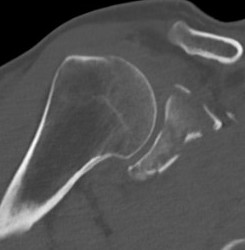

Type II: Fracture glenoid fossa that exits laterally

Definition

Transverse fracture through glenoid fossa

- inferior triangular fragment

- exits lateral border scapula